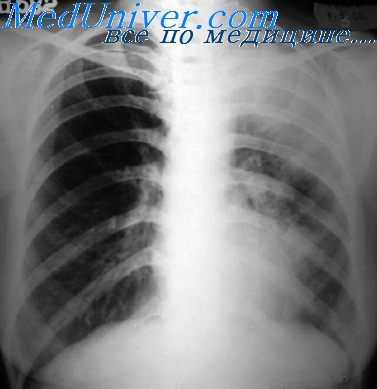

- Лучевая диагностика. Обязательным методом обследования при подозрении на пневмомедиастинум является рентгенография грудной клетки в двух проекциях. На рентгеновских снимках определяются полосы газа, подчёркнута медиастинальная плевра, чётко очерчены контуры средостения. Анализ рентгенограмм в динамике позволяет выявить нарастание эмфиземы. В неясных случаях показана КТ грудной полости.

Проводится тщательное рентгенологическое обследование (рентгенография грудной клетки, томография, рентгенография пищевода, пневмомедиастинография). Рентгенологически при медиастините может выявляться расширение тени шеи и средостения, эмфизема средостения, пневмоторакс, гидроторакс, уровень жидкости в средостении, пищеводные свищи.